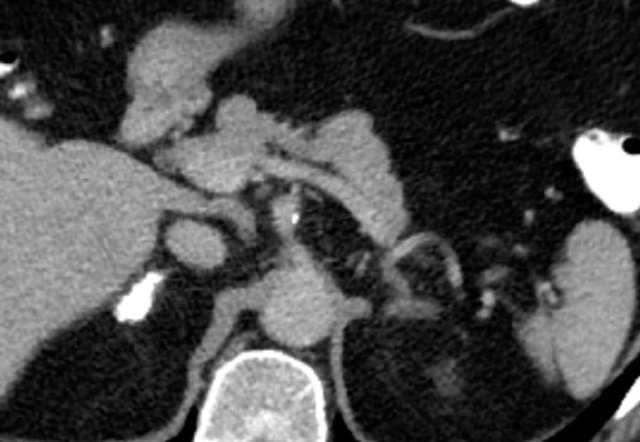

This axial venous CT shows a very bulky right adrenal mass, suspicious for a malignancy, based on the large size and heterogeneity.

This lesion is an adrenocortical carcinoma, but in contrast to the former example, subsequent FDG PET-CT performed for staging purposes showed only mild uptake and only in the most avidly enhancing part of the tumor.

Most adrenocortical carcinomas show intense FDG-uptake.

This lack of FDG-avidity might be due to a lower grade tumor with lower mitotic rate or large hemorrhagic or necrotic components.